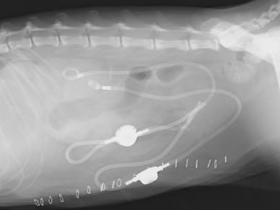

他院より紹介されたケース、この猫ちゃんは左右尿管に 結石(矢印)が詰まっていました。

尿管結石が原因で腎臓は水腎症になっていました。

尿管結石を取り除き人工尿管(SUBシステム2.0)を設置しました。

水腎症は改善しました。